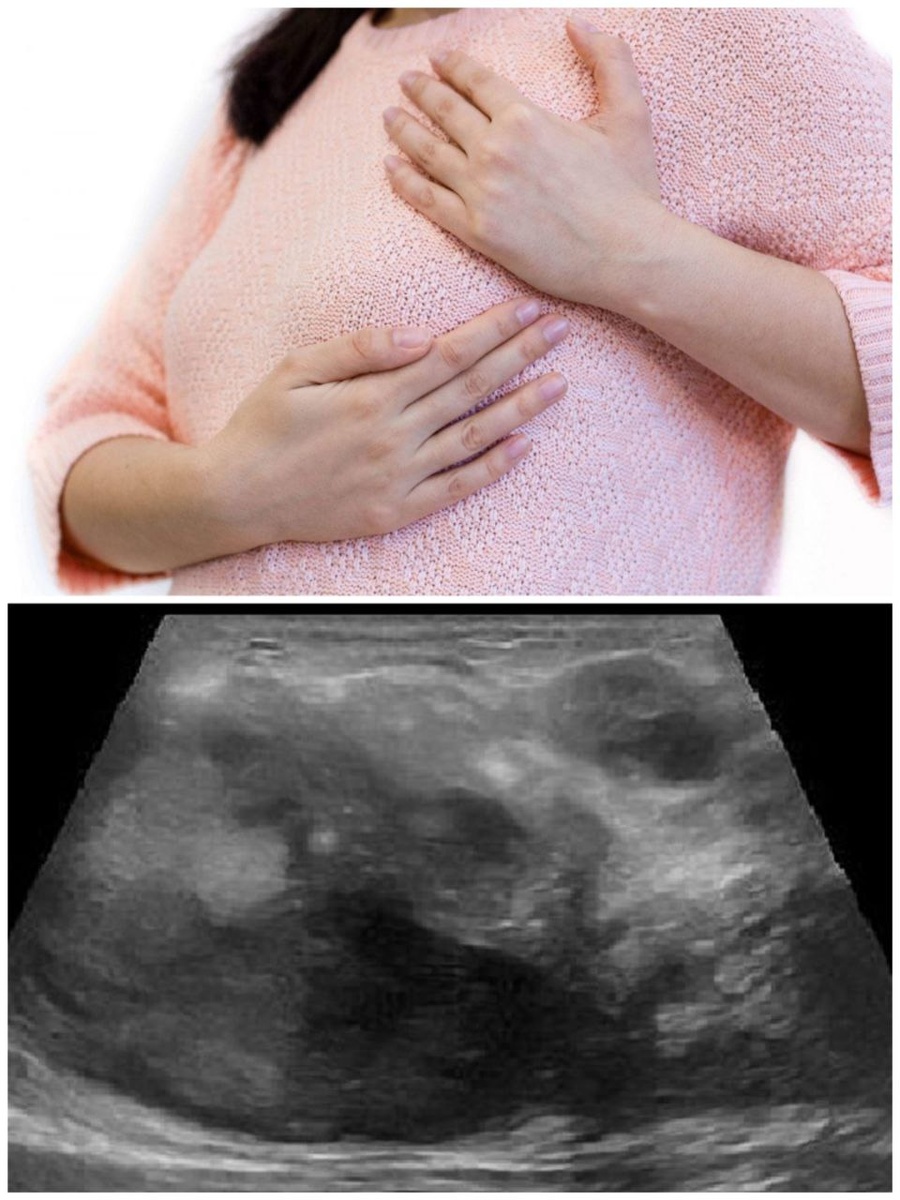

Каникулы прошли, а тревога только росла. Только в середине января Марина сделала УЗИ в своей поликлинике. Заключение: BIRADS 4 – подозрительное образование, требующее срочной консультации онколога.

На повторном УЗИ у маммолога картина изменилась: выраженный отёк и гипоэхогенный участок – сформировался абсцесс (гнойник) в молочной железе.